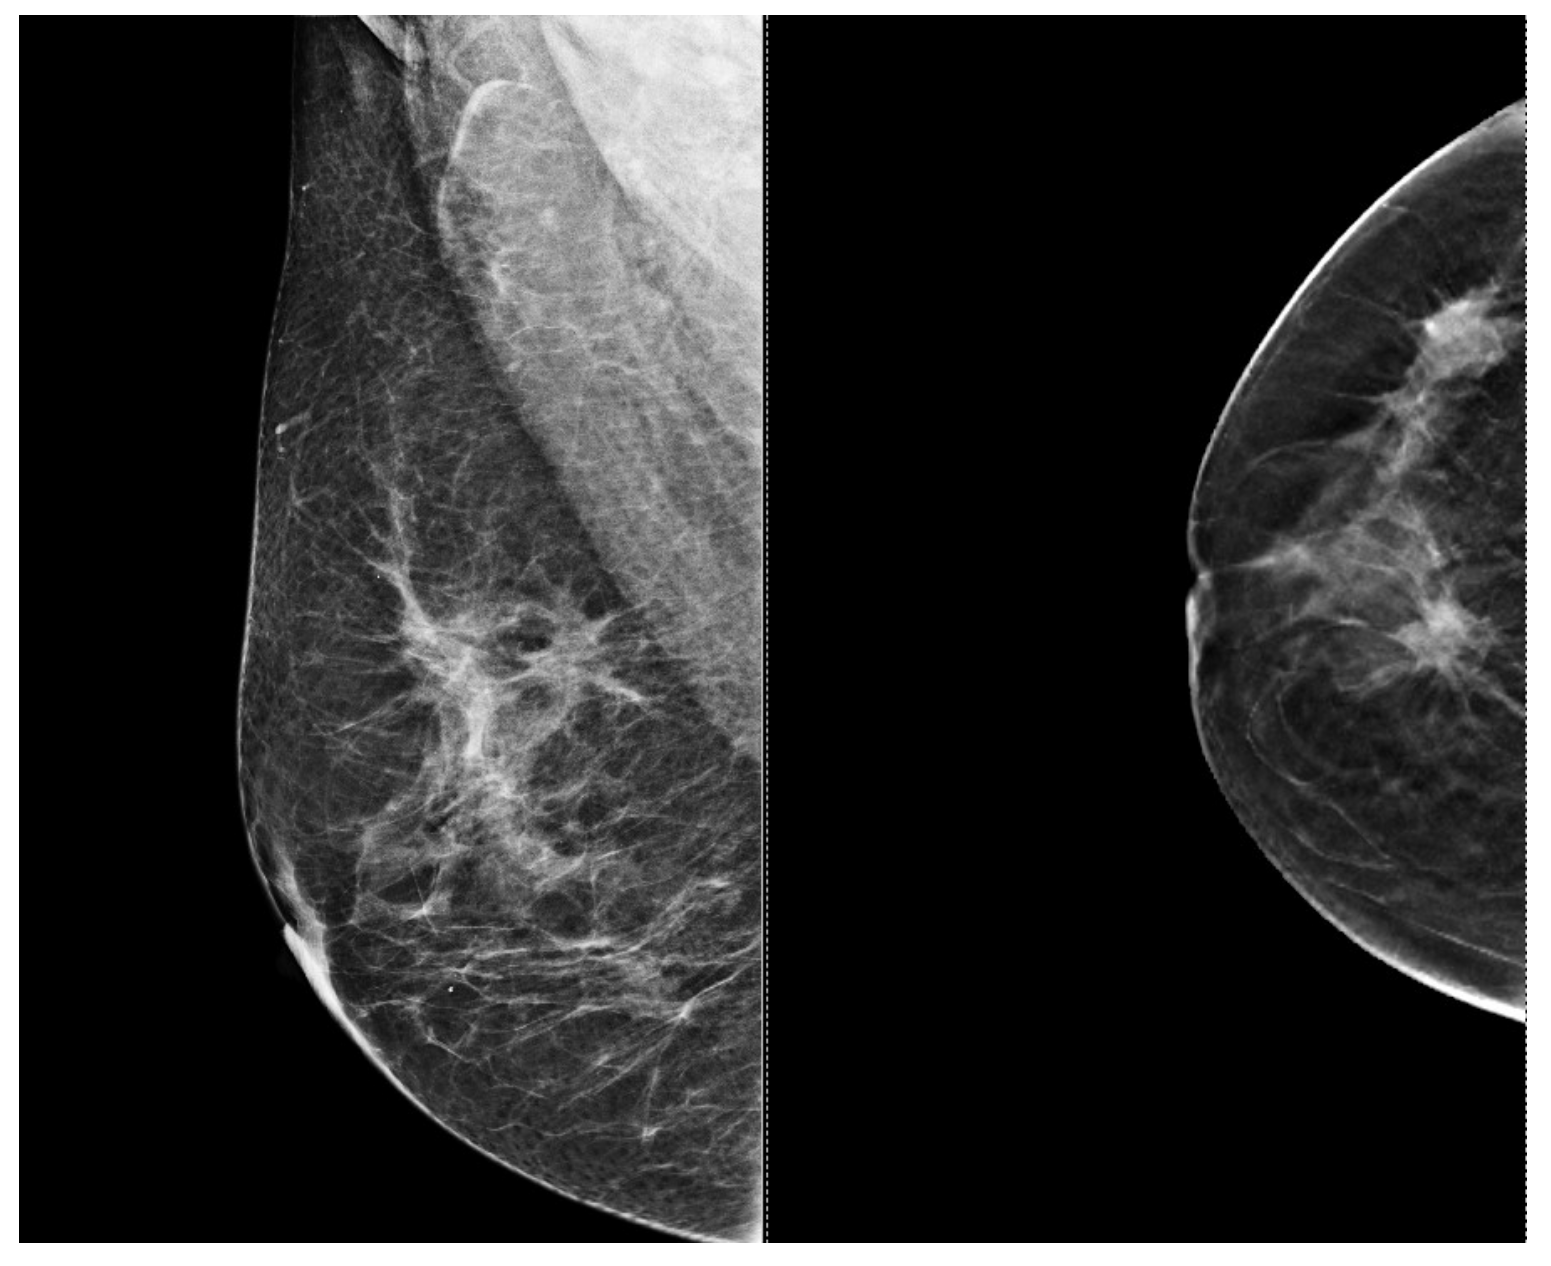

Figure 4.

Mammography of the left breast shows a spiculated and ill-defined lesion, that associates skin retraction.

Figure 3 and Figure 4, same suspicious lesion seen both on ultrasound and on mammography in the left breast, presenting ill-defined margins and spiculations on both imaging methods.